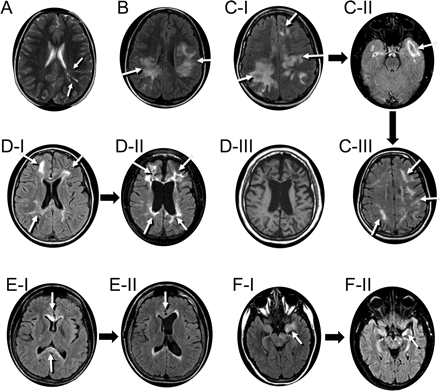

图1代表MRI异常与半球参与七个孩子的典型光谱中确定儿童中枢神经系统AQP4自身免疫

白色箭头表示异常液体衰减反转恢复(天赋)或T2信号。(一)病人1(8岁女孩展示与脑病)T2信号异常辐射触角的方式沿着Virchow-Robin空间通过顶叶皮层下白质从侧脑室。(B)病人2(12岁女童出现谵妄紧随其后昏迷,前面描述的14)主要支流白质异常。(我)病人3(15岁女孩出现谵妄和失语症)主要支流白质异常;1年后,双时态皮层病变被认为(C-II);病人除了轻微认知正常表达性失语症(C-III)。(d - i)患者4(8岁女孩展示脑病和癫痫)触角从侧脑室白质异常辐射到额叶和顶叶白质。随访MRI 8年后(D-II和D-III)演示了持久化天赋异常和全球萎缩。(练习)病人5(17岁女孩与11年历史的脱髓鞘疾病)膝的支流T2异常超过胼胝体压部;图片3年后揭示解决膝损伤(E-II)和脑积水(分流的;看到图3中,A和B)。(f i)患者6(15岁男孩出现脑病,焦点运动发作,和轻偏瘫)天赋信号异常在左侧中央颞区和大脑脚离开了。图片3年后(F-II)展示持久化天赋异常和左海马萎缩。